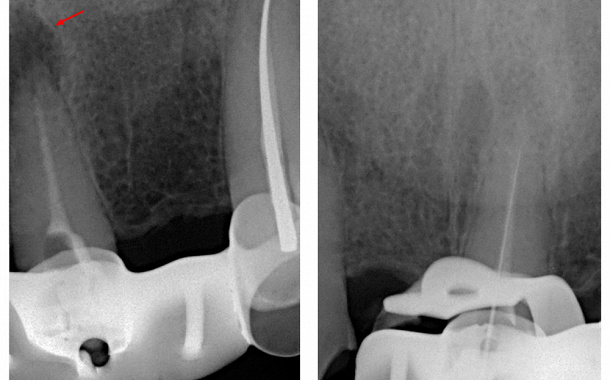

Глубокий кариес – распространяется на зубную пульпу, где находятся нервы и кровеносные сосуды, ведет к тотальному разрушению структур зуба с частичным вовлечением в процесс пульпы зуба. Глубокий кариес может вызвать острую боль и требует срочного лечения.

Пациент может жаловаться на боль в зубе, возникающую от механических или химических раздражителей. При осмотре доктор обнаруживает глубокую кариозную полость, в которой находится размягченный дентин. Иногда отмечаются ноющие болевые ощущения в зубе, сохраняющиеся после удаления раздражителя. Если разрушение затрагивает пульпу, для восстановления зуба потребуется лечение корневых каналов.

- Проведение корневого каналоведения в случае поражения зубной пульпы.